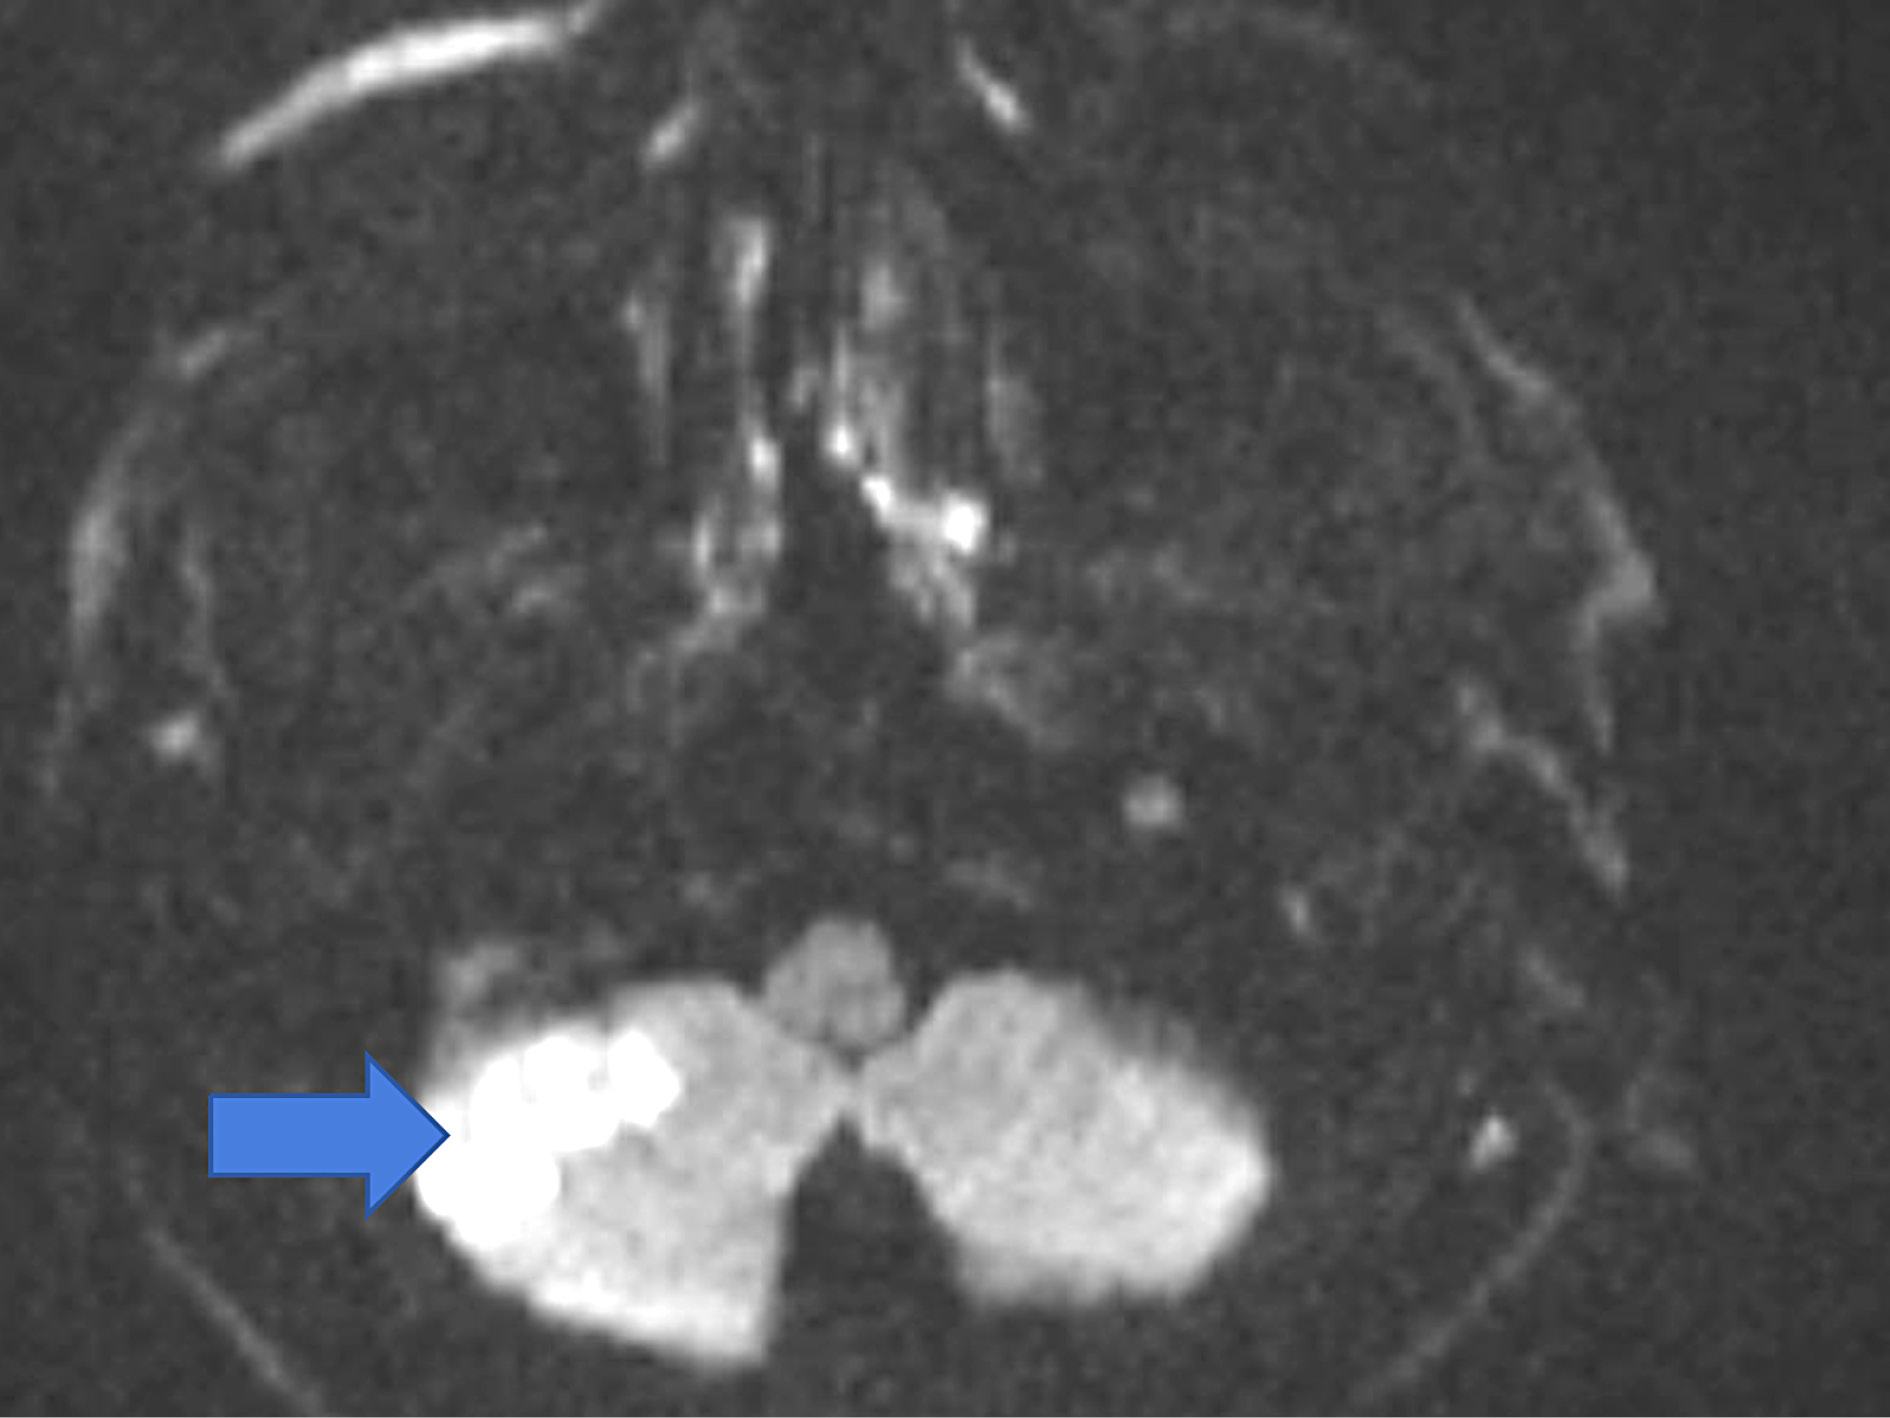

The results of routine blood, biochemistry, whole blood and vitamin B12 tests were normal. Elisa tests were negative. Complete urinalysis was within normal limits. Results of HLAb5 tests for vasculitis, thrombophilia, Fabry and Behçet’s were normal. No acute pathology was detected in the brain computed tomography (CT). Magnetic resonance imaging (MRI) revealed diffusion restriction in the right cerebellum (Figure 1).

Magnetic resonance angiography revealed the blood flow disorder at the vertebral artery level at the right atlanto-occipital junction. The patient was diagnosed with the cerebellar infarction secondary to neck hyperextension and was treated conservatively with acetylsalicylic acid 300 mg 1×1 and omeprazole 1×1. Within nine days his gait and cerebellar signs improved. He was recommended neurology follow-up and discharged at the end of the tenth day.